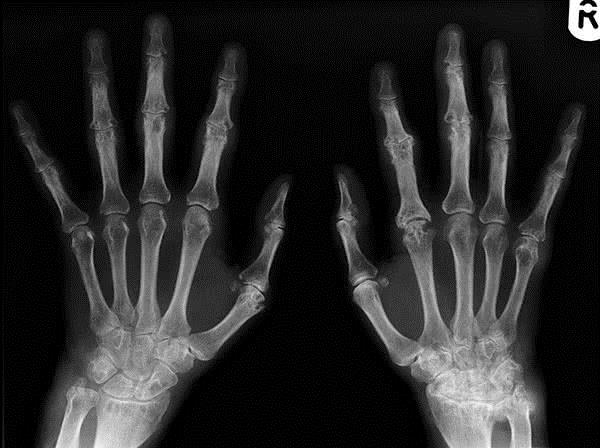

Рентгенография позволяет выявить отсутствие деформирующих явлений в суставах. Деформация обычно не наблюдается. Так как рентген свидетельствует об отсутствии значимых деформаций.

Главную роль в постановке диагноза РА играют биохимический анализ крови, рентгенологические суставные изменения и вышеперечисленные симптомы.

В случае наличия симптомов полиартрита на протяжении одного года и более длительного времени следует проводить рентгенографию рук и ступней. Своевременная диагностика полиартрита имеет очень большое значение. Ведь только при правильной и оперативной терапии больной сможет упредить появление повреждений суставов и иных серьезных нарушений.